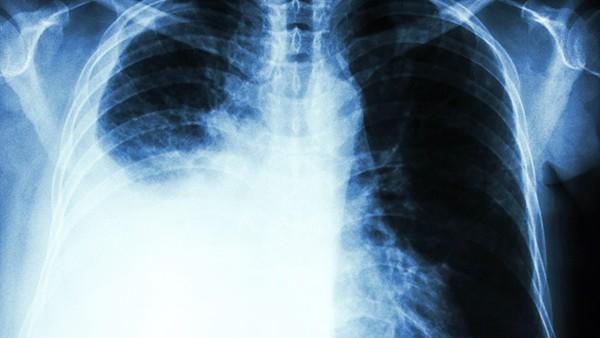

胶质母细胞瘤(Glioblastoma Multiforme, GBM)是一种最常见且最具有侵袭性的成人脑肿瘤,其生物学特性和临床表现都具有高度的异质性。为了对胶质母细胞瘤进行早期诊断、分期评估、治疗效果监测以及复发风险评估,磁共振成像(MRI)作为一种高分辨率的影像学检查手段,在临床中发挥着至关重要的作用。

MRI具有优良的软组织对比度,在肿瘤成像、周围水肿评估以及病灶周围脑组织的变化等方面表现出色。其在胶质母细胞瘤检测中的应用主要包括以下几个方面:

肿瘤定位与大小评估:MRI可以精准定位肿瘤在脑中的位置及其体积,有助于外科手术的规划和实施。通常,胶质母细胞瘤在T1加权成像(T1WI)下表现为低信号或等信号,而在T2加权成像(T2WI)和FLAIR序列下则表现为高信号。

肿瘤的侵袭性评估:胶质母细胞瘤常常具有明显的侵袭性,其边界模糊,通常伴随明显的周围水肿。在MRI影像中,肿瘤的扩散及其对邻近组织的侵犯程度能够通过对比相关信号变化得到评估。

肿瘤静态与动态观察:采用对比增强MRI,可以更清晰地显示肿瘤的血管生成情况以及肿瘤的增强模式。GBM通常在对比增强扫描中表现为不均匀强化,这与其复杂的血供及坏死区域密切相关。

治疗效果监测:术后以及放疗、化疗后的随访可以通过MRI检查评估肿瘤的残留情况、复发风险以及周围组织的反应。胶质母细胞瘤的复发可能表现为新的异常信号区或增强区,这些变化可通过MRI进行早期检测。